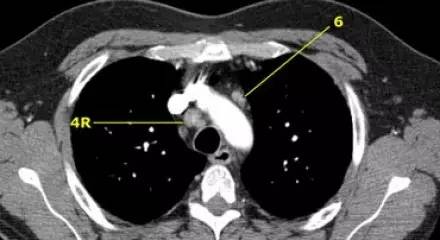

肺 CT 横断面右下气管旁淋巴结(4R )和主动脉旁淋巴结(6)